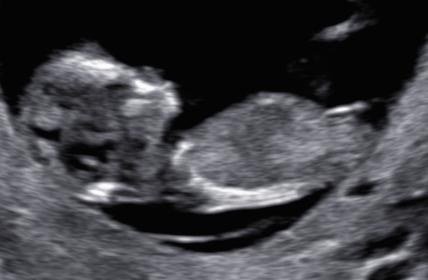

Just finished with NT scan and by lmp im 11w6d (although clinic said 12 weeks) and baby measures ahead at 12w5d. Any more thoughts with these? I have a video too but cant figure out how to blank out my name in it lol.

Attachment 27789Attachment 27790Attachment 27791Attachment 27792Attachment 27793Attachment 27794Attachment 27795